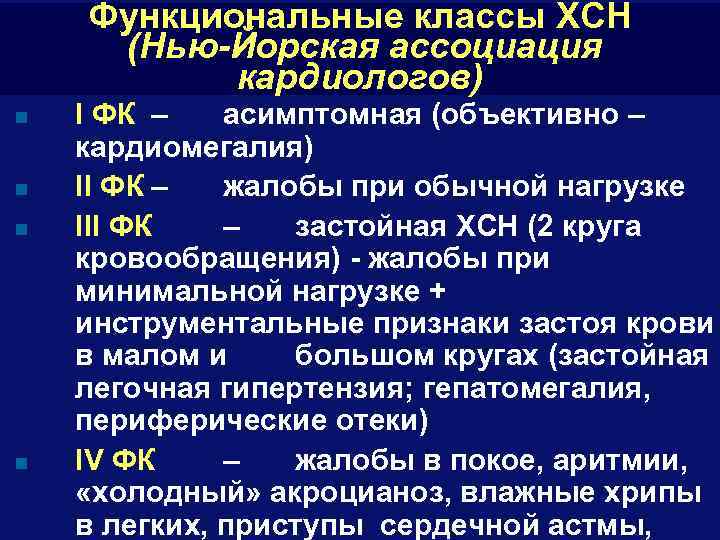

Функциональные классы ХСН (Нью-Йорская ассоциация кардиологов) n n I ФК – асимптомная (объективно – кардиомегалия) II ФК – жалобы при обычной нагрузке III ФК – застойная ХСН (2 круга кровообращения) - жалобы при минимальной нагрузке + инструментальные признаки застоя крови в малом и большом кругах (застойная легочная гипертензия; гепатомегалия, периферические отеки) IV ФК – жалобы в покое, аритмии, «холодный» акроцианоз, влажные хрипы в легких, приступы сердечной астмы,